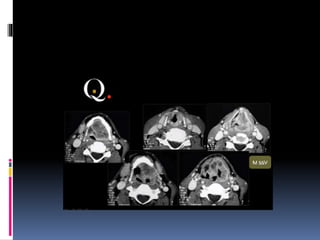

CT NOSE AND PNS

BASIC CONCEPTS

 CT scans typically obtained for visualizing the

paranasal sinus should include coronal and axial (3-

mm) cross

sections.

 Soft tissue and bony windows facilitate evaluation

of disease processes and the bony architecture.

 The use of intravenous contrast material just prior

to scanning can help define soft tissue lesions and

delineate vascularized structures, such as vascular

tumors.

 Contrast-enhanced CT is particularly useful in

evaluating neoplastic, chronic, and inflammatory

processes.

 The CT scan is the GOLD STANDARD

investigation in all preoperative cases as it gives

detailed bony anatomy of the area and serves as

a ‘road map’ for the operating surgeon.

 CT scans are best done after a course of

antibiotics, so that acute inflammation is not

mistaken for chronic mucosal disease.

CORONAL CUTS